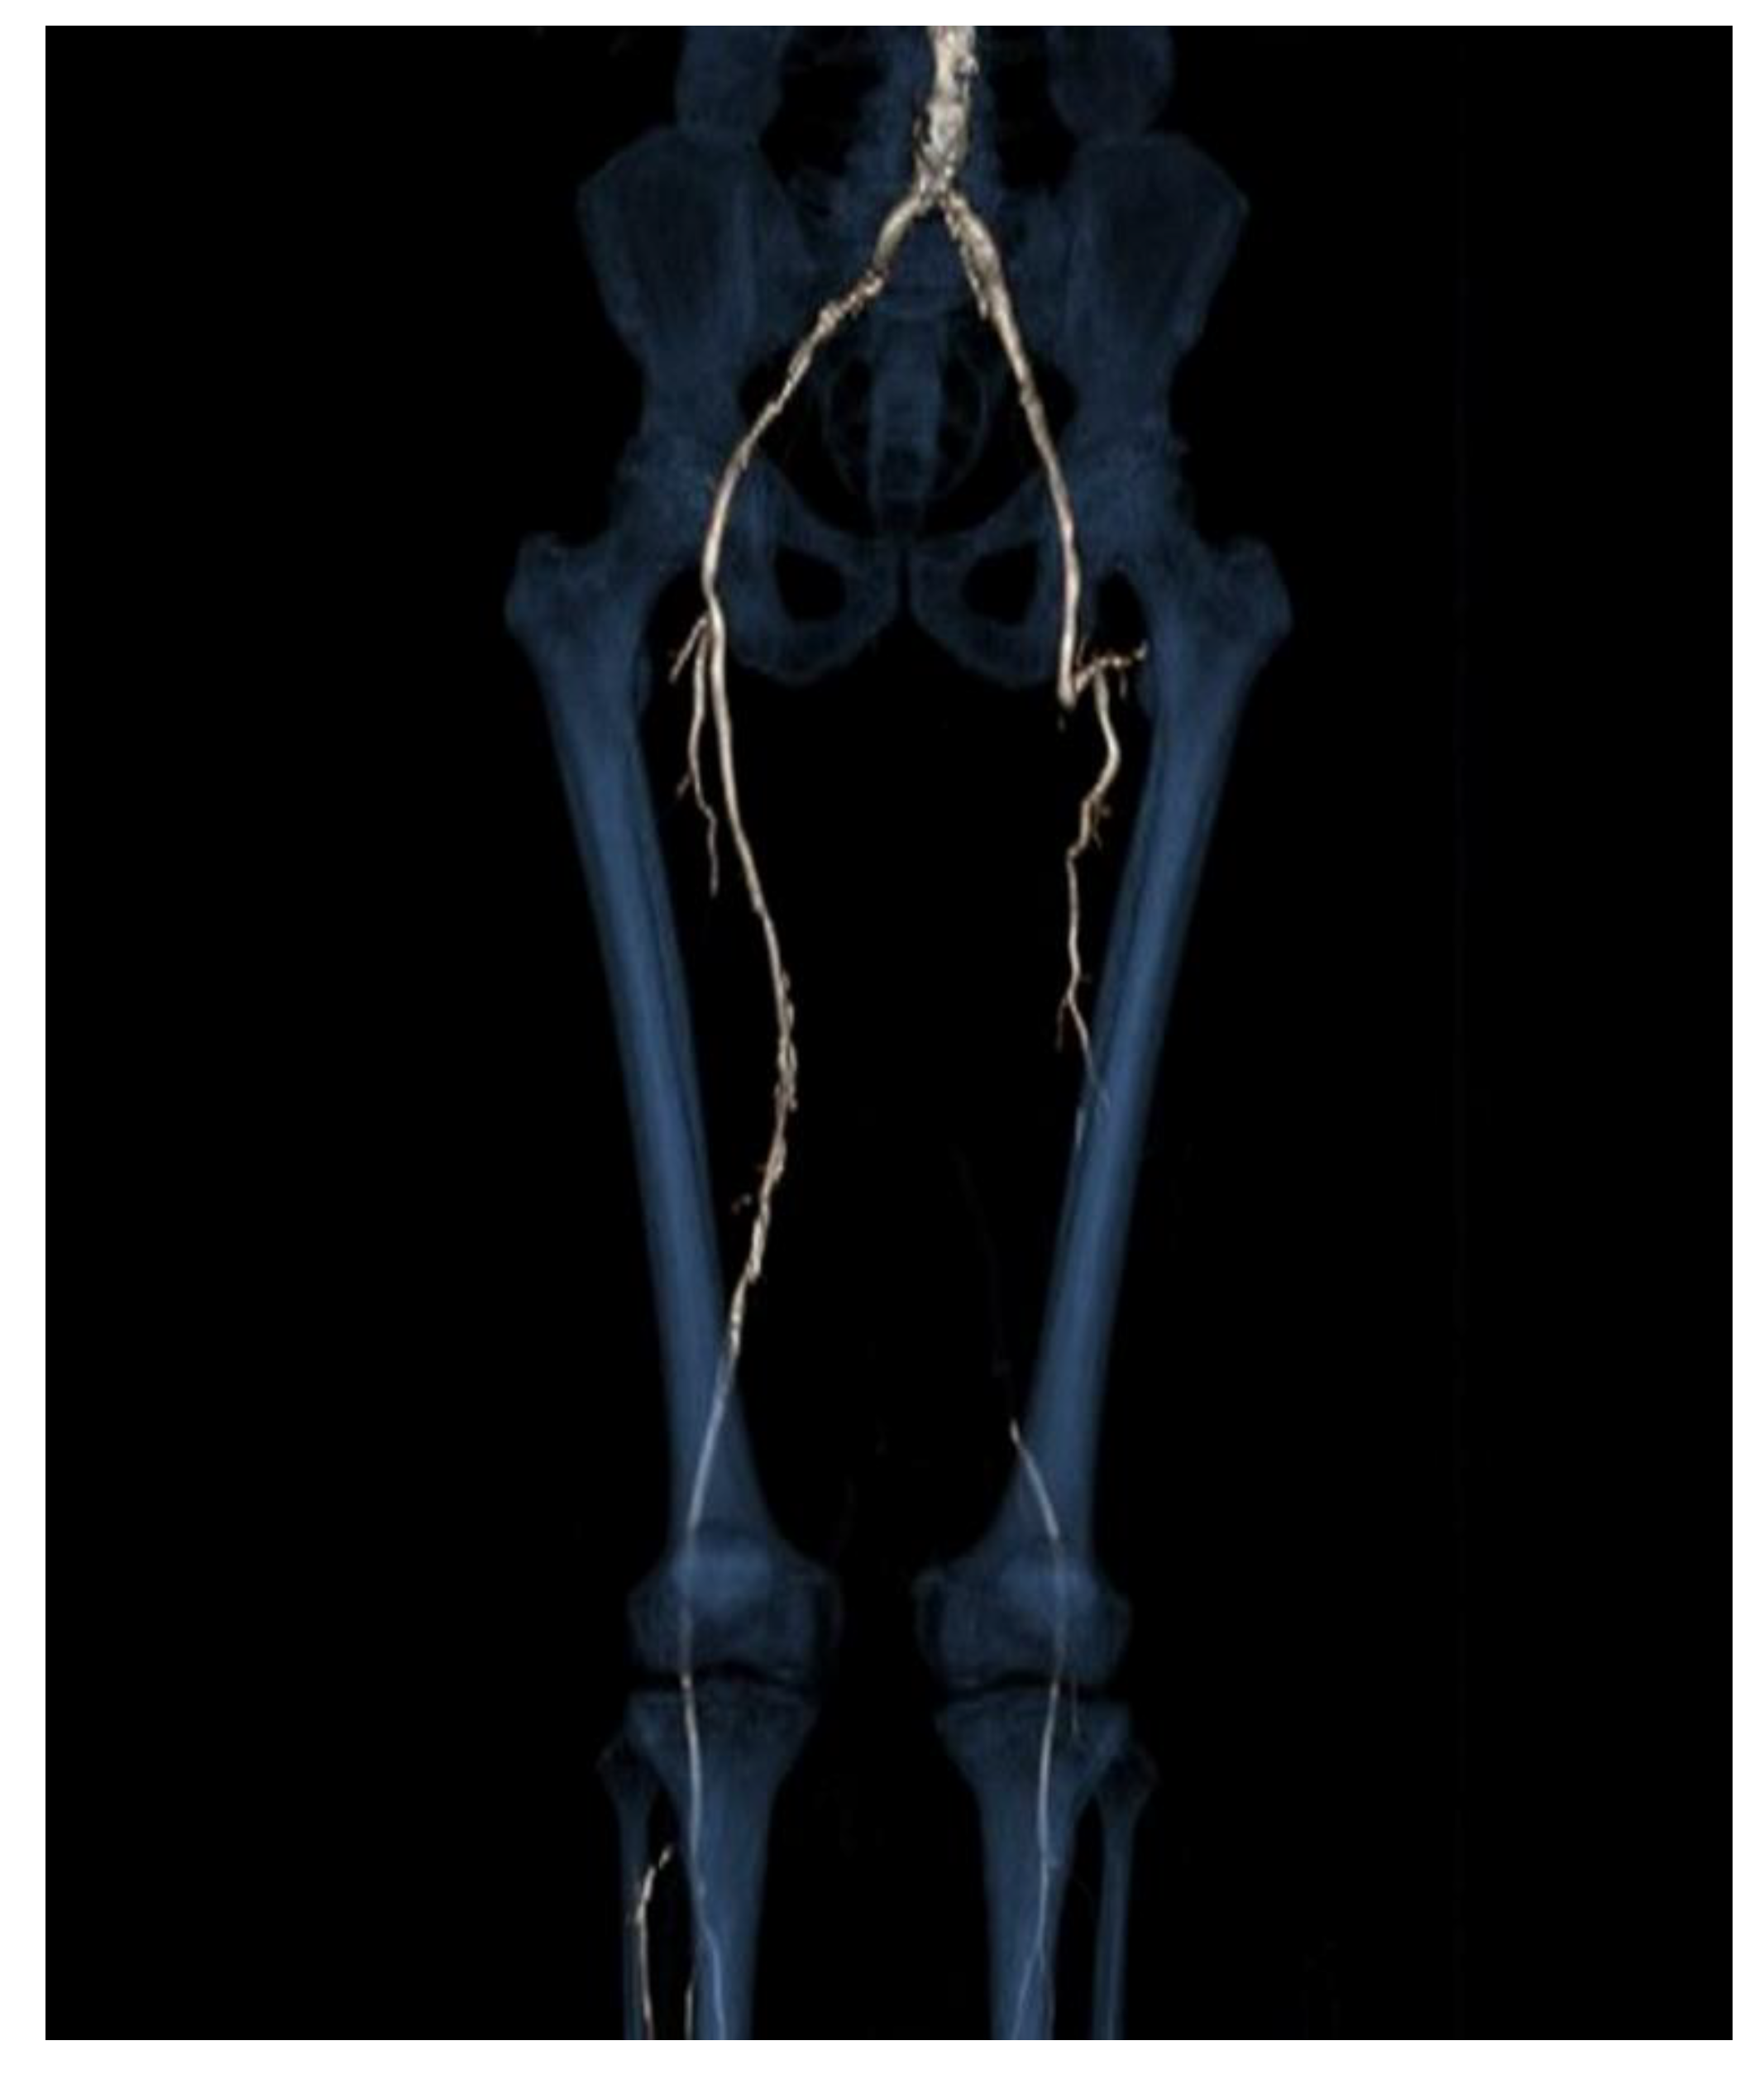

On clinical examination, he had leg pain and swelling. There was no presence of motor or sensory deficits. Rutherford classification Grade II, Category 4, with AP < 38 mmHg. The angio-CT scan of the abdomen and lower limbs revealed that the iliac artery, common femoral artery and deep femoral artery of the left side were atheromasic but patent, whereas the FP bypass was completely occluded (Figure 1). At distal anastomosis, a PA which measured 31 × 38 × 55 mm was present (Figure 2a–c). The left popliteal artery was revascularized by collateral vessels coming from the deep femoral artery. On the right side, there was regular patency of the leg arteries.

Figure 1. Three-dimensional reconstruction image from angio-CT scan. It shows complete occlusion of FP bypass on the left side; iliac artery, common femoral artery and deep femoral artery of left side are atheromasic but patent.